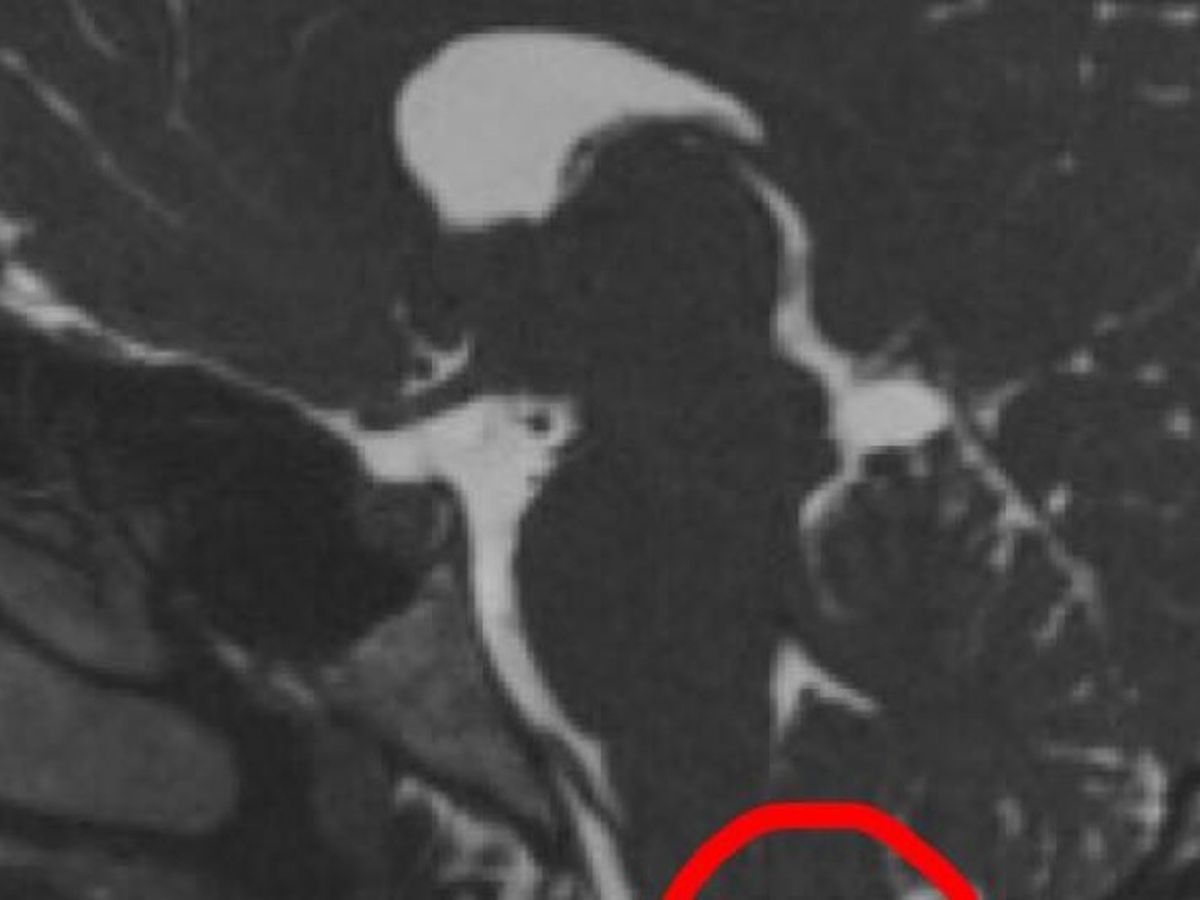

I am Jamie-Eloise King, I'm 19 years old and for the last 9 years I have been suffering symptoms from a brain condition called Arnold Chiari Malformation Type 1. This is when part of my brain (the cerebellar tonsils) are too big for my skull so they drop through into my spinal canal. I suffer from debilitating headaches at the front and back of my head which have gradually got worse over the last 9 years. I also suffer from from nausea, vomiting, dizziness, numbness, sharp pains in my legs, spine, arms and head. My list of symptoms goes on. Here in the UK I have seen 4 Chiari neurosurgeons and a number of neurologists who have all dismissed my case and are not willing to help me. I have found a Chiari neurosurgeon in America who is willing to do surgery, this will mean having my cerebellar tonsils removed. If I don't have this surgery done, I will never feel better and my quality of life will worsen. To have this operation, I need to raise £150,000. I will be holding fundraising events and any donations made I will be very grateful for. I do have a Facebook page if anyone would like to read my story and be updated on my progress.